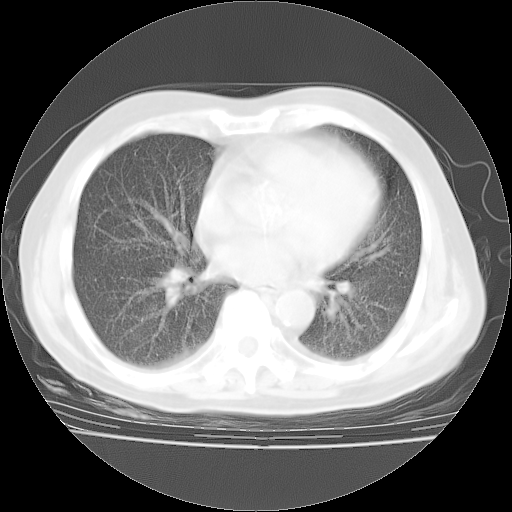

4月28日肺部CT——再次出现类似去年5月9日——磨玻璃样、间有“粟粒样”改变。

4月28日肺部CT